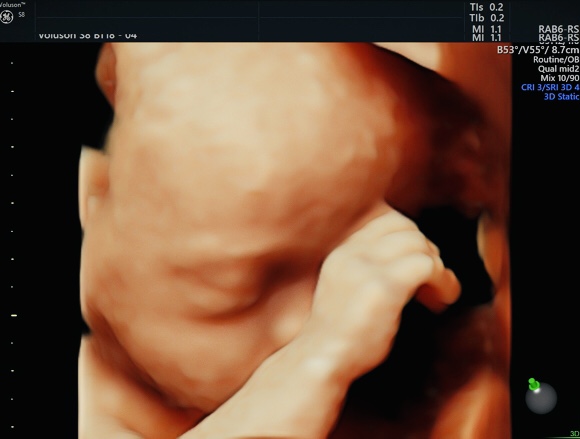

4D超音波外来について

当院に通院中の妊婦さんは、妊婦健診と一緒に4Dエコーを施行できるようになりました。(18週以降)